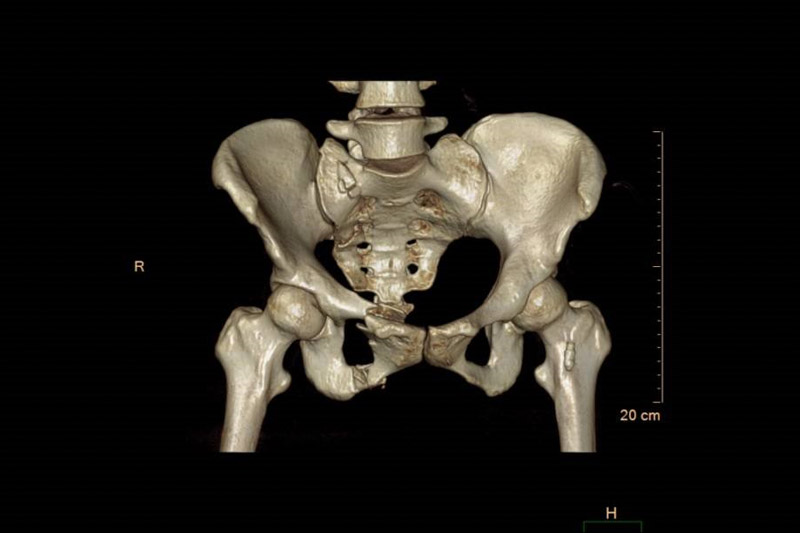

患者周女士在走路時(shí)不慎被車撞傷,被120送至當(dāng)?shù)蒯t(yī)院,清醒后感覺臀部劇痛難忍,雙髖活動(dòng)受限,為求進(jìn)一步治療,轉(zhuǎn)入了柳州市人民醫(yī)院創(chuàng)傷骨科,經(jīng)CT檢查,患者為骨盆骨折,需手術(shù)治療。

創(chuàng)傷骨科專家團(tuán)隊(duì)經(jīng)過周密的術(shù)前討論,決定術(shù)中采用智能可視化機(jī)器人作為“新助手”,輔助精準(zhǔn)定位,為患者行骨盆骨折經(jīng)皮微創(chuàng)內(nèi)固定術(shù)。不同于表面軟組織,經(jīng)皮微創(chuàng)骨科手術(shù)無法直視,更像是在堅(jiān)硬的暗箱內(nèi)操作。骨科手術(shù)機(jī)器人突破了傳統(tǒng)手術(shù)中“手”“眼”的局限,術(shù)前對(duì)患處進(jìn)行影像掃描并進(jìn)行詳細(xì)規(guī)劃,手術(shù)中醫(yī)生可以通過機(jī)器人的“透視眼”,將虛擬手術(shù)計(jì)劃轉(zhuǎn)變?yōu)楝F(xiàn)實(shí)空間位置,手術(shù)路徑更加精確,穿刺針的長(zhǎng)度、寬度和進(jìn)入骨骼的角度更加準(zhǔn)確。